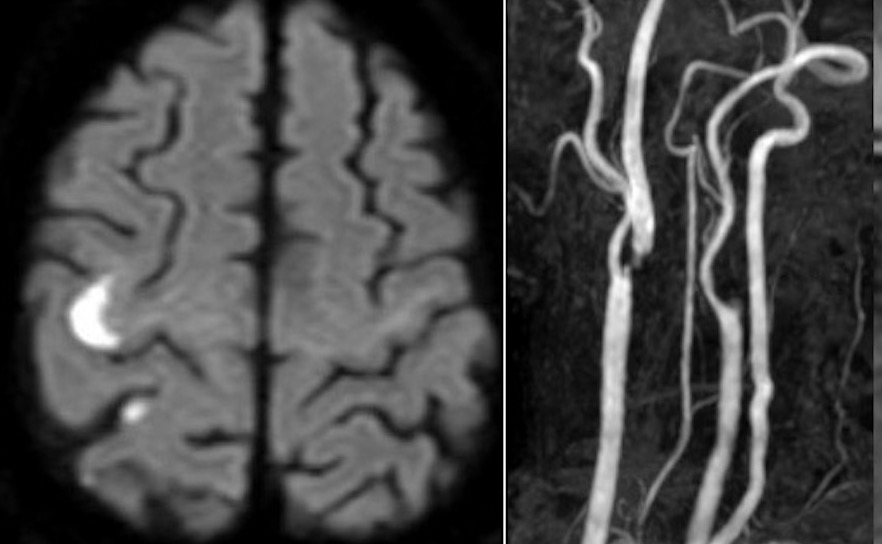

内頸動脈狭窄

251021火 75歳男性、左内頸動脈閉塞、両側椎骨動脈狭窄を伴う右内頸動脈狭窄症に対してCEAを行いました。